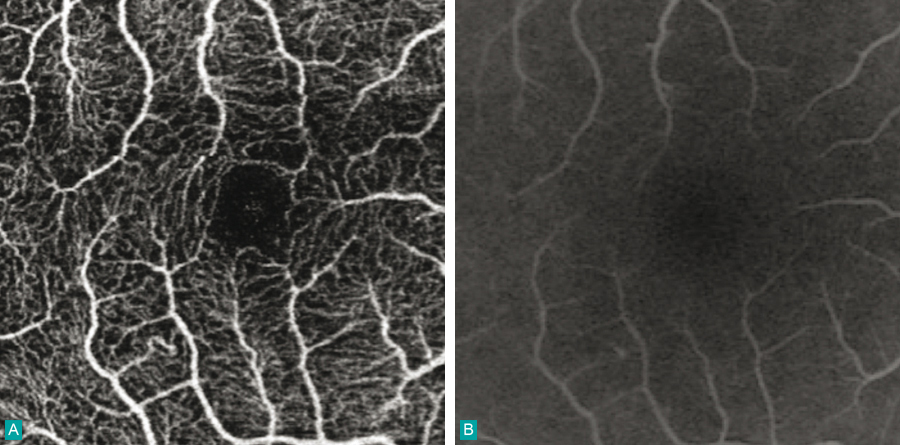

Angiographie-OCT.A. Pôle postérieur de la rétine en angiographie-OCT.B. Le même cliché en angiographie à la fluorescéine avec injection de colorant.La trame vasculaire est mieux visible en angiographie-OCT. OCT : tomographie en cohérence optique.